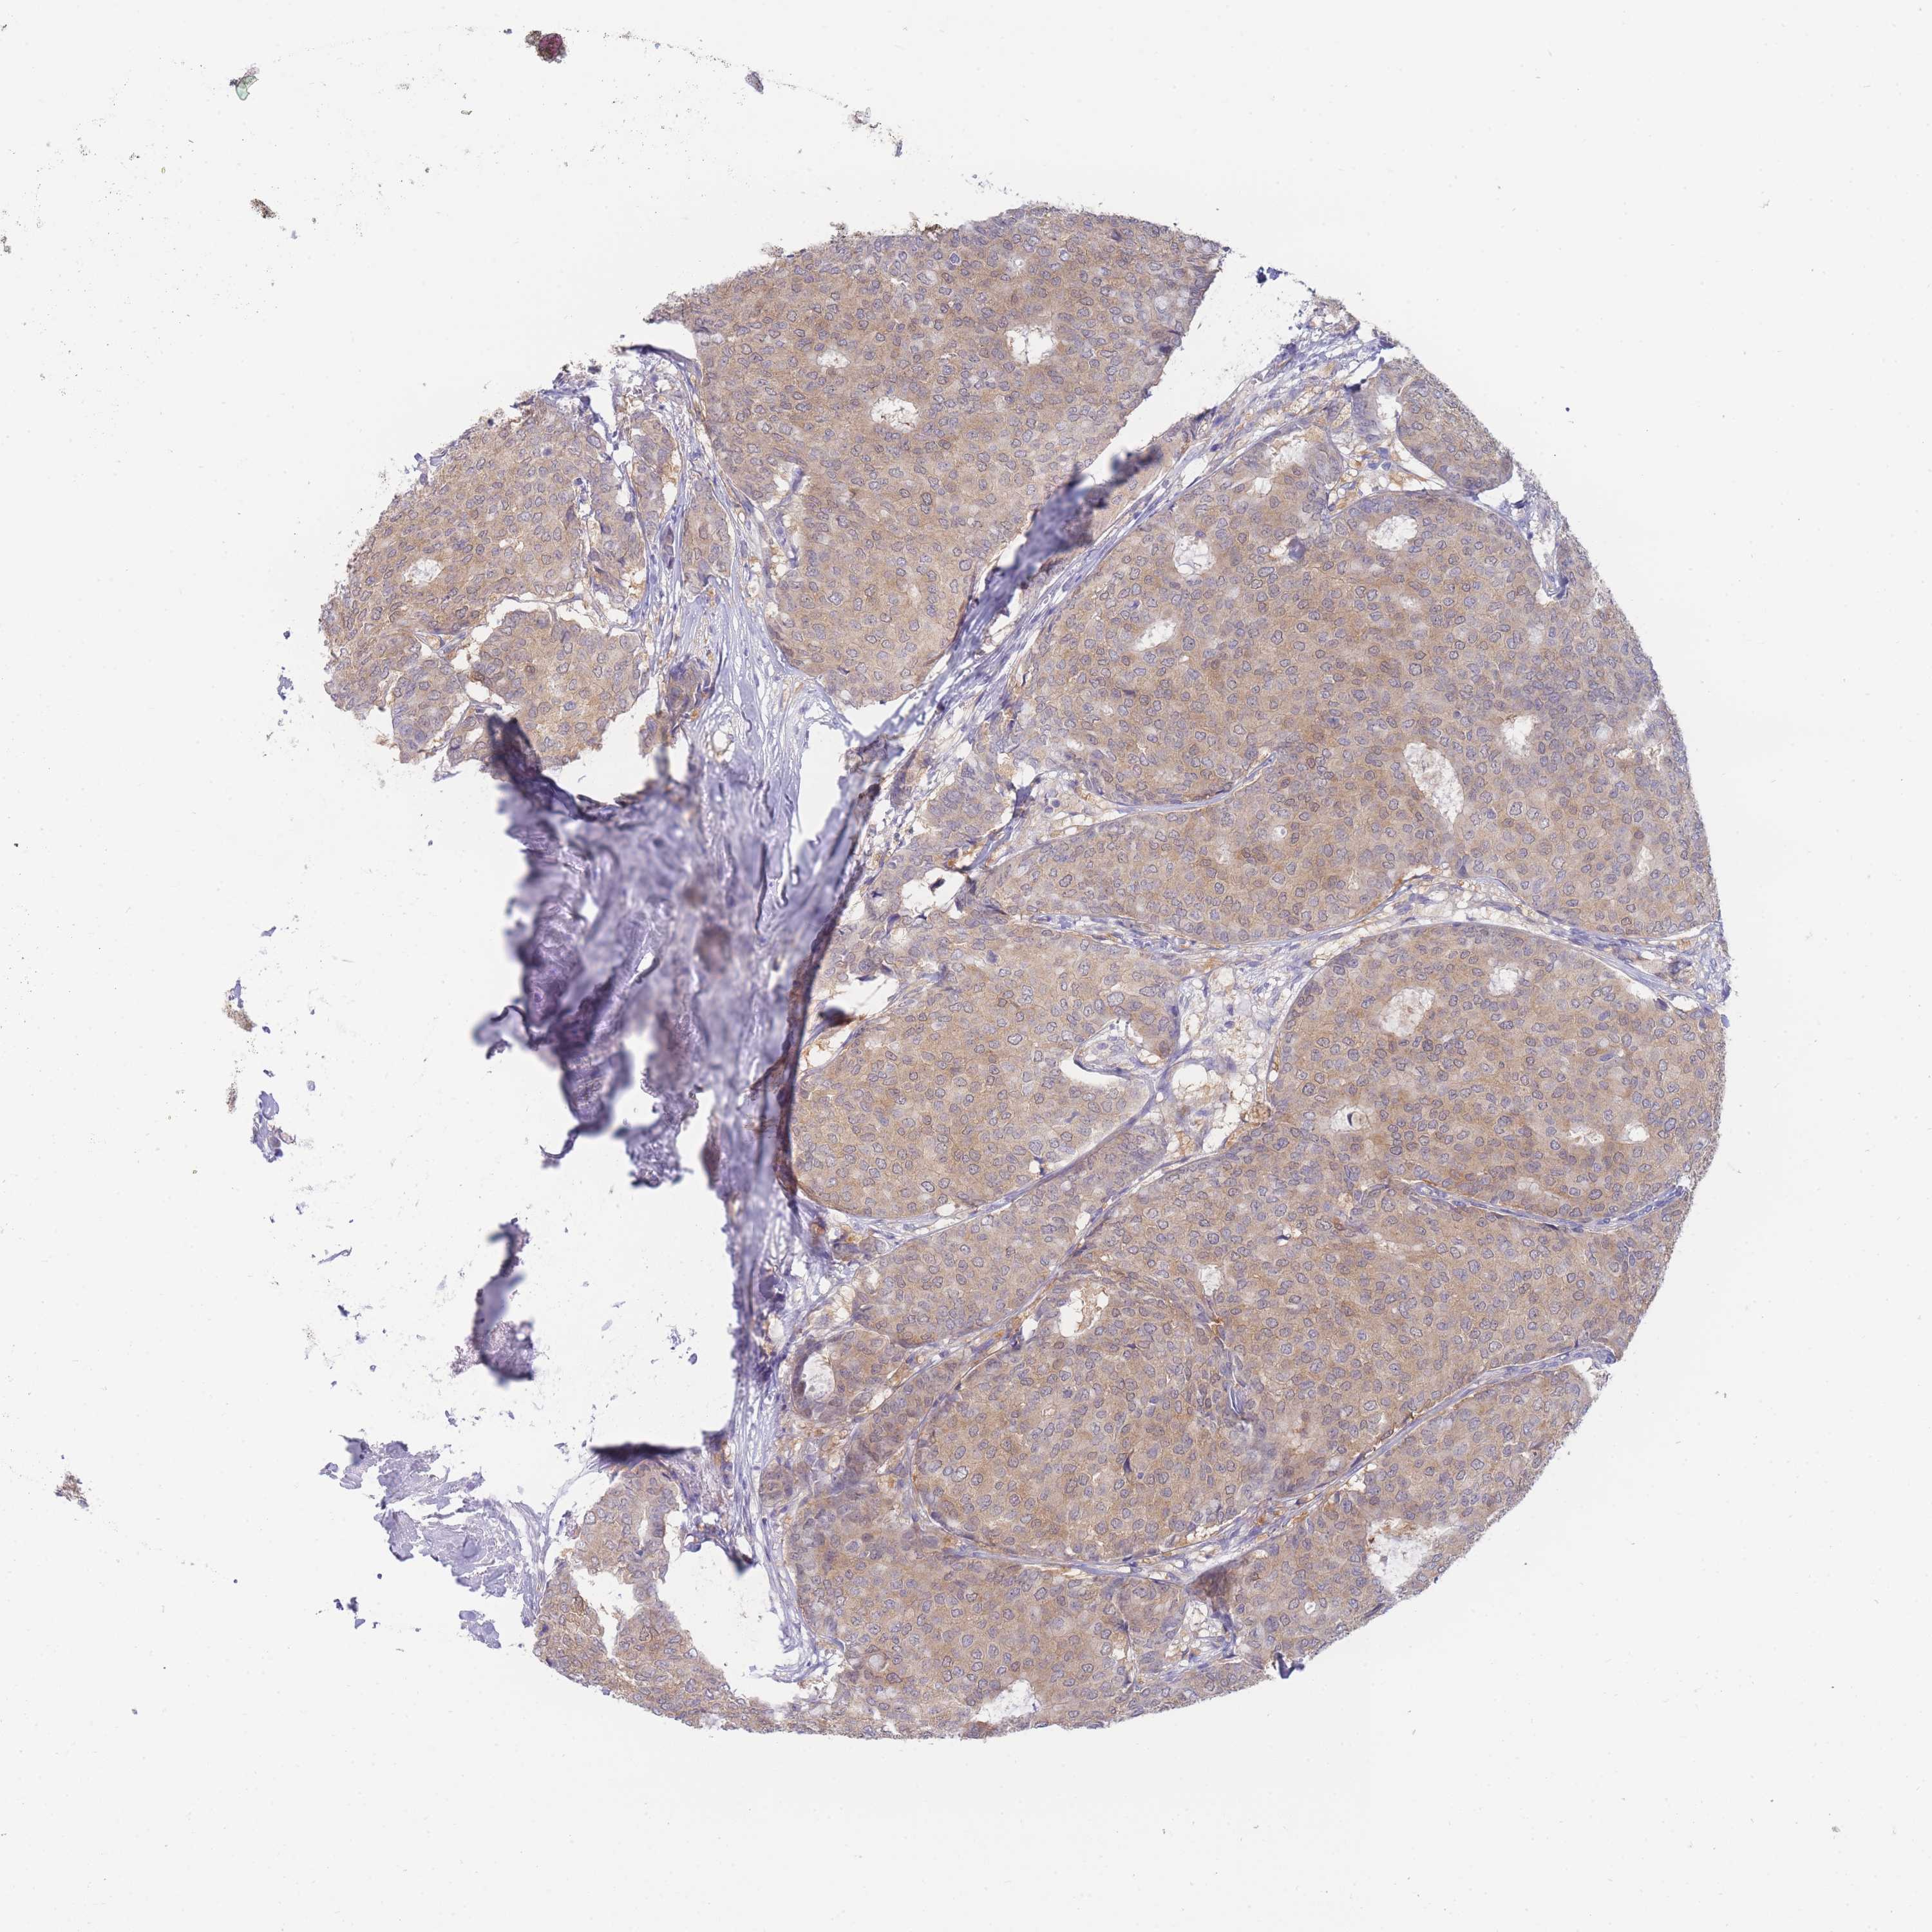

BRCA TCGA BRCA VALIDATION PROTEIN EXPRESSION